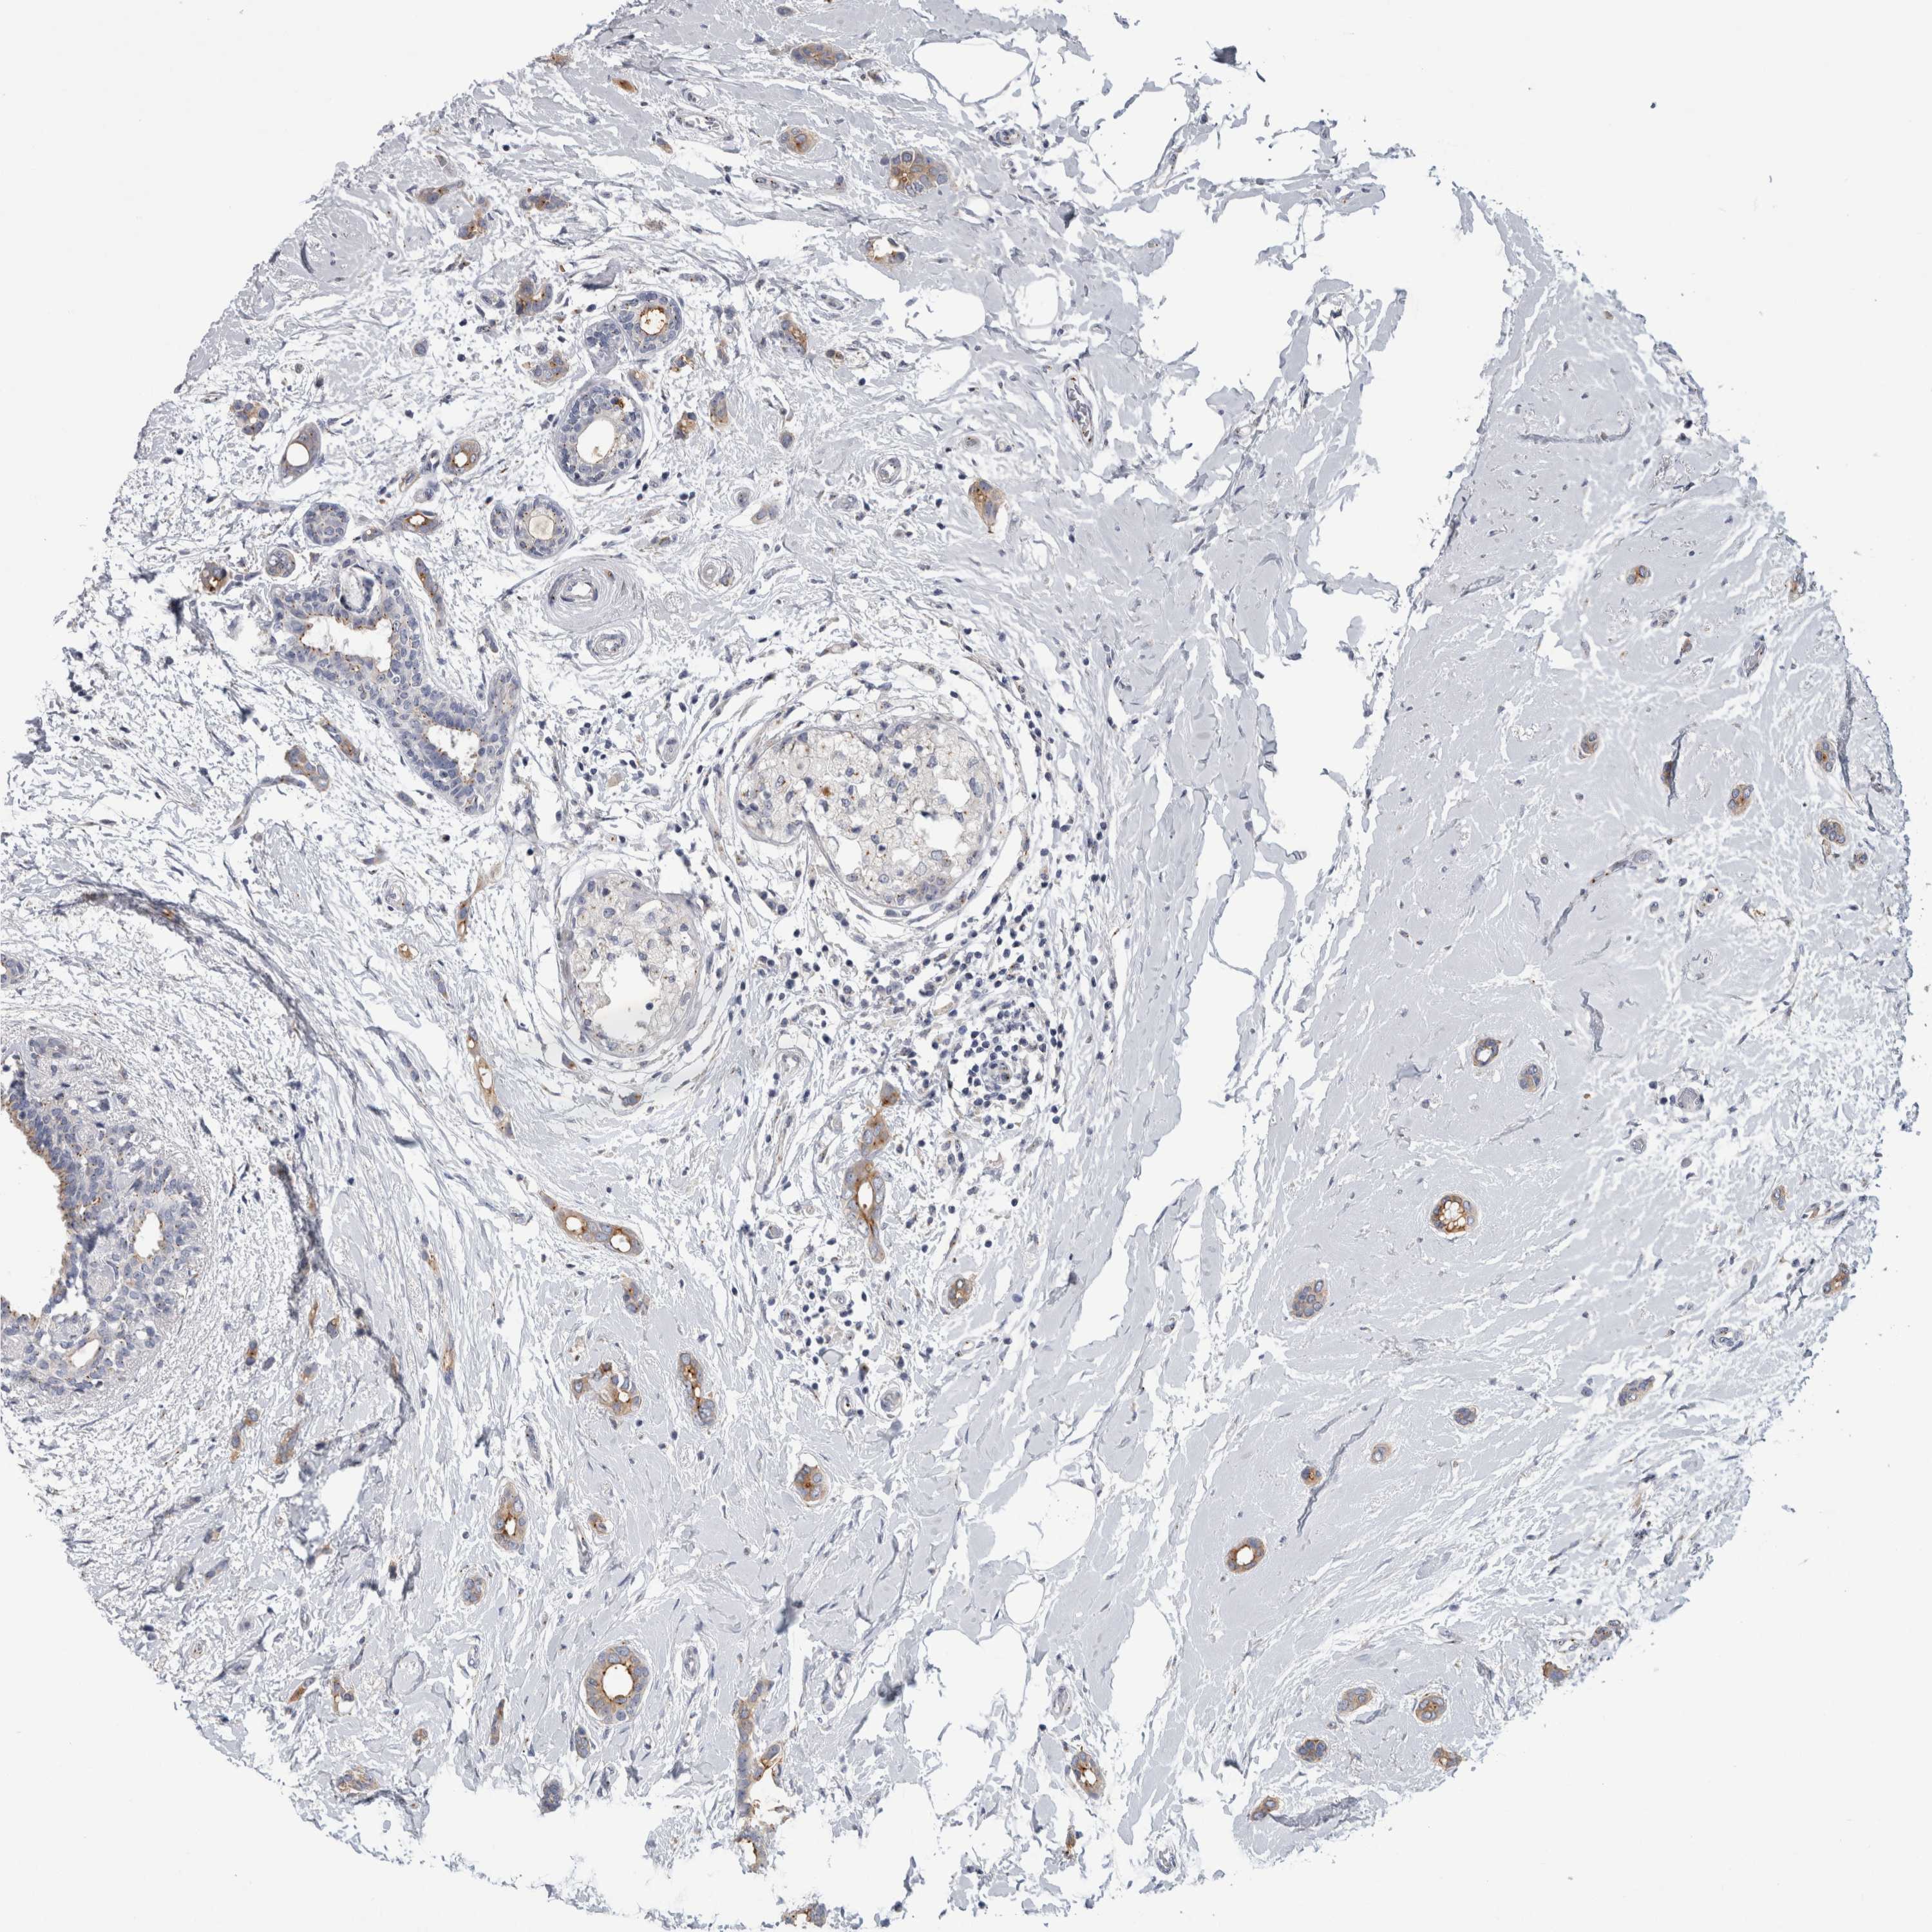

BRCA TCGA BRCA VALIDATION PROTEIN EXPRESSION

ANTIBODIES

AND

VALIDATION